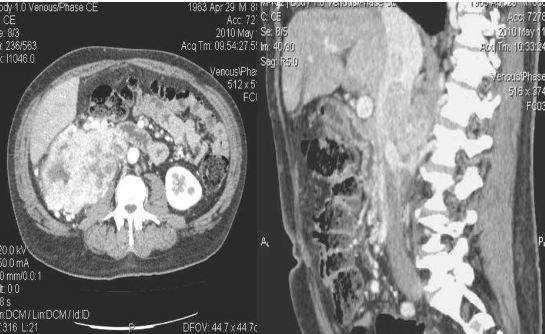

При визуализации картина при пиелонефрите или абсцессе почки схожа с картиной при опухоли, поэтому результаты анамнеза, осмотра и других клинических данных помогают радиологу в постановке правильного диагноза. В представленном случае визуализируются гиподенсные образования в обоих почках. Если диагноз базировать только, исходя из данных изображения, то напрашивается следующий дифференциальный ряд: пиелонефрит, лимфома или метастаз.

Данный пациент поступил с жалобами на боль в боку и с анамнезом воспалительного поражения мочевыводящих путей, также у пациента отрицательный онкологический анамнез, поэтому диагноз — пиелонефрит.

На КТ спустя 4 месяца визуализируются нормальные почки. На первом изображении патологическая картина обусловлена мультифокальным пиелонефритом.